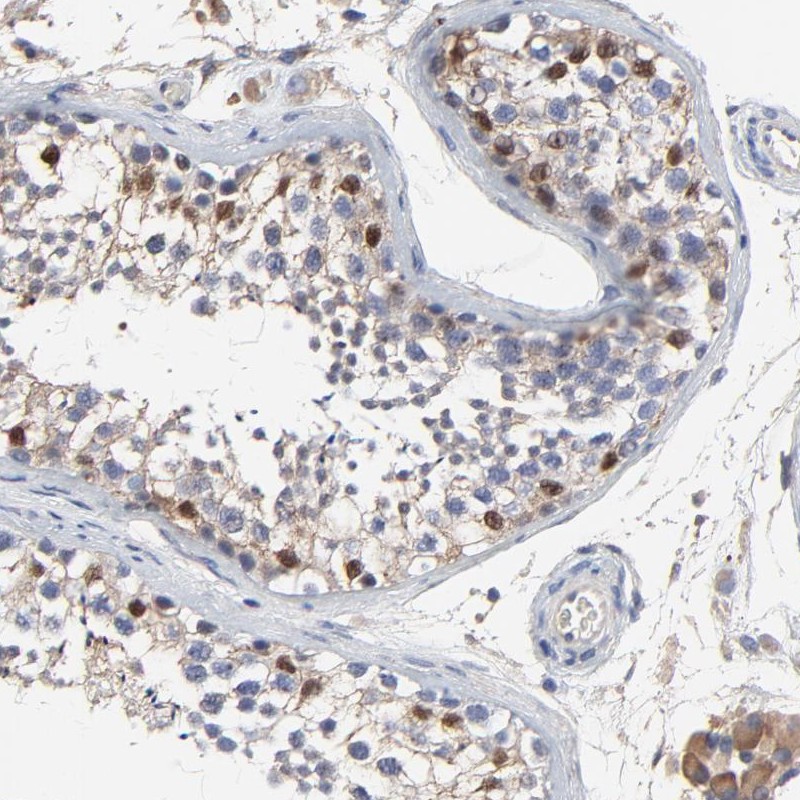

Immunohistochemical staining of human testis shows strong nuclear and cytoplasmic positivity in cells in seminiferus ducts, Leydig cells expressed moderate cytoplasmic staining.